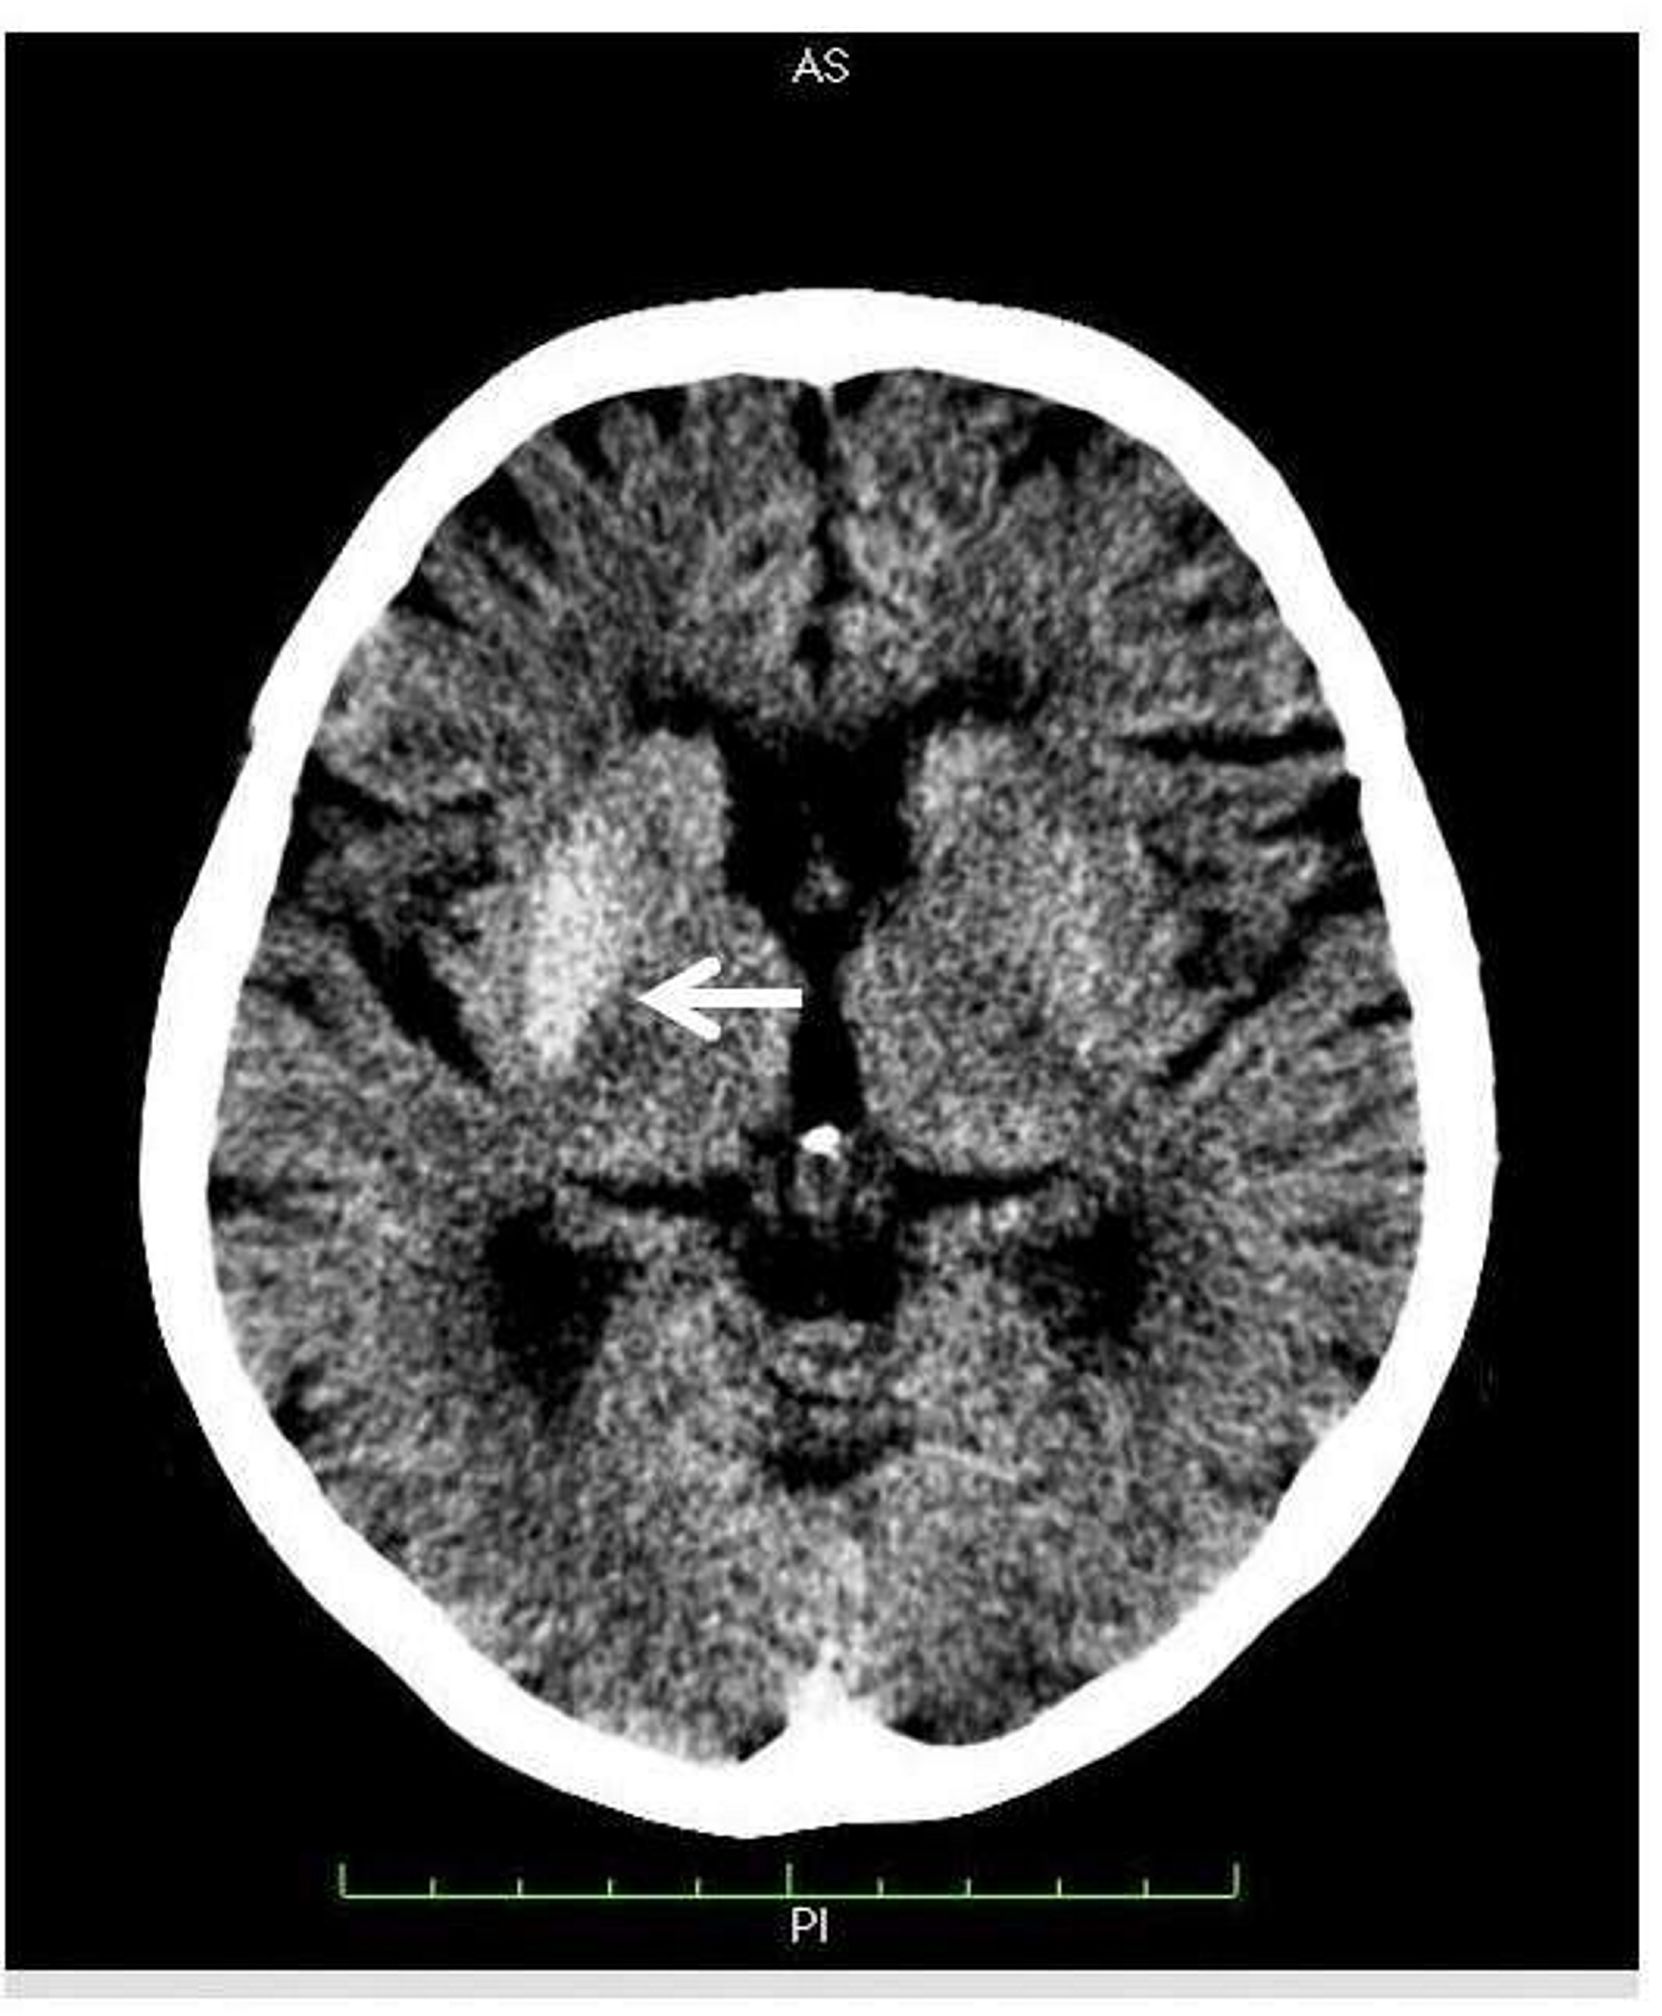

A hemicoreia-hemibalismo (HCHB) faz parte de um espectro de movimentos contínuos e involuntários de uma parte do corpo. Dentre as causas está o Diabetes mellitus. A apresentação de HCHB no estado hiperglicêmico configura-se como uma manifestação rara desse distúrbio metabólico sistêmico, e é associado a alterações nos exames de imagem cerebral, como a tomografia computadorizada, constituindo-se numa síndrome de caracterização e estudos recentes e de poucos relatos na literatura. Trata-se de uma paciente que apresentou abertura do quadro de Diabetes mellitus tipo 2 com HCHB, além de queixas de poliúria e polidipsia, apresentado, à admissão, glicemia capilar ao acaso de 586 mg/dl. A tomografia de crânio evidenciou leve hiperdensidade nos gânglios da base à direita. Após o controle dos níveis glicêmicos, a paciente apresentou melhora progressiva até remissão total do quadro em um período de 30 dias, com nova imagem tomográfica revelando completo desaparecimento da lesão neurológica inicial.